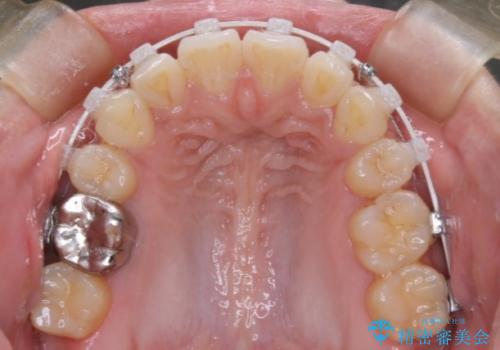

前歯の前突と口元の突出感を改善|上下左右4番抜歯+審美ワイヤー矯正

- 前歯の突出が強く、口元が前に出ている印象を改善するため、上下左右の第一小臼歯(4番)を抜歯する矯正治療を計画しました。抜歯により得られたスペースを利用して、前歯を後方へと移動させて整列します。治療には目立ちにくい透明な審美ブラケットとワイヤーを使用し、毎月1回の調整を行いながら徐々に歯を動かし、約2年で口元全体を整える計画としました。

前歯が前に出ているため口元が突出し、唇が閉じにくいなどの悩みを抱えておられました。治療にあたり上下左右の第一小臼歯を抜歯し、十分なスペースを作ることで前歯を効果的に後方へ移動させました。装置には透明で目立ちにくい審美ブラケットを採用し、治療中の審美的ストレスを軽減しました。定期的な調整を通じて無理なく確実に歯列を整え、前歯の突出感を解消。治療後は口元の印象が自然で美しく改善され、患者様には非常にご満足いただけました。